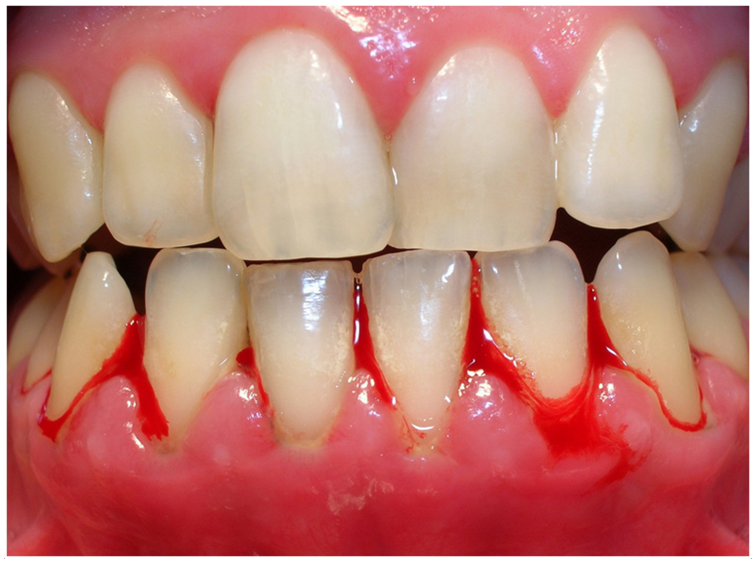

Gingival Inflammation and Redness

In the early stage, the gums become swollen, tender, and red because of inflammation caused by plaque buildup (Armitage, 1995; Newman et al., 2022).

Bleeding Gums

Bleeding often happens during brushing, flossing, or sometimes even without touching the gums. This is a key sign of gum inflammation (Newman et al., 2022)